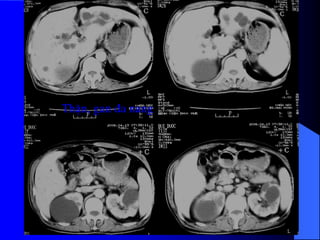

3.5. Tháûn âanang Tháûn âa nang laì bãûnh di truyãön. Nang coï nguäön gäúc tæì nephron. Thæåìng xaøy ra åí hai tháûn, nãúu tháúy tháûn âa nang mäüt bãn thç bãn kia coï báút thæåìng kên âaïo hån, nhæîng nang nhoí hån. Khoaíng 50% træåìng håüp kãút håüp våïi nhæîng báút thæåìng khaïc nhæ nang gan, nang tuûy, nang laïch, tuïi phçnh âäüng maûch naîo. - Trãn phim buûng coï thãø tháúy boïng tháûn låïn gáy dáúu hiãûu âáøy håi trong ruäüt (häüi chæïng khäúi), xoïa båì cå thàõt læng cháûu.

• 66.

- Trãn NÂTMmä tháûn caín quang khäng âäöng nháút. Khi ÂBT nhuäüm âáöìy TCQ tháúy bãø tháûn heûp theo chiãöu ngang, tàng theo chiãöu doüc. Caïc âaìi tháûn bë keïo daìi, maính deí, lãûch hæåïng do nhiãöu nang âeì vaìo. - Trãn siãu ám phaït hiãûn tháûn âa nang, ngay caí åí giai âoaûn såïm, tháûn låïn våïi ráút nhiãöu nang nhoí. Khi nang bë nhiãùm khuáøn hay xuáút huyãút seî tháúy cáúu truïc ám cuía caïc nang khäng âäöng nháút, thaình nang daìy, väi hoïa. Siãu ám âäöng thåìi coï thãø tháúy nang åí gan hoàûc tuûy, laïch trong häüi chæïng Von Hippel - Lindau.